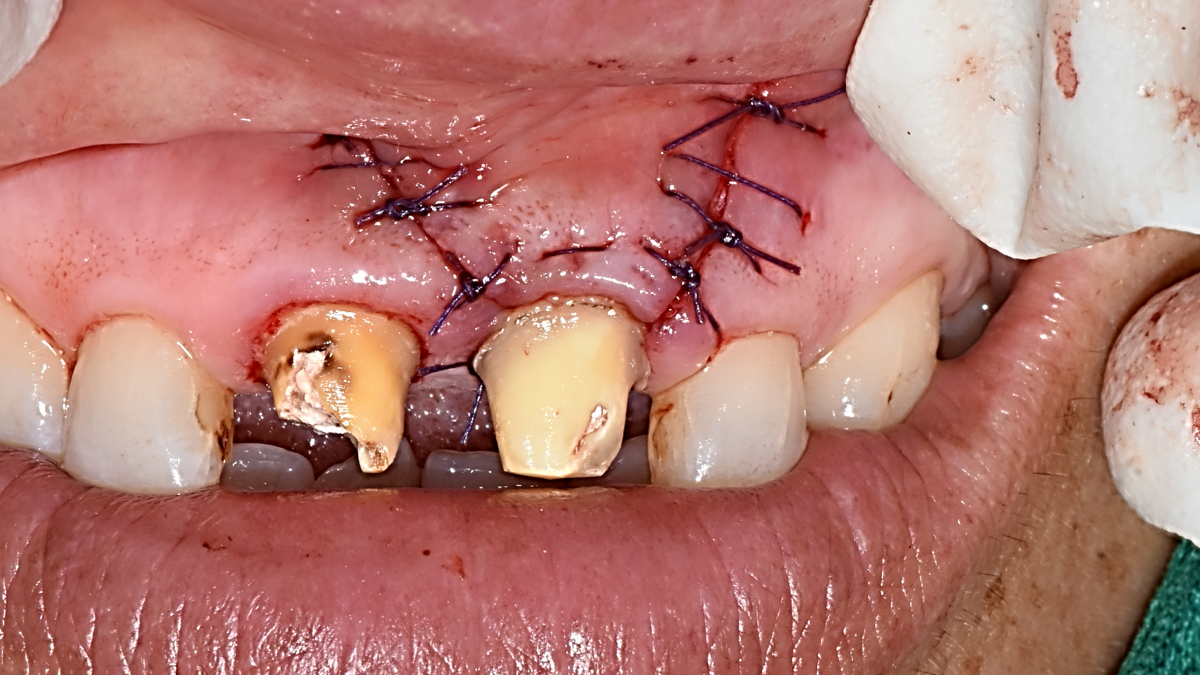

Apicorctomy /central incisor /GBR ; 6-year follow up.

<CJ SBN> Apicorctomy /central incisor /GBR ; 6-year follow up.

▲CBCT. Left central incisor had a apical lesion.